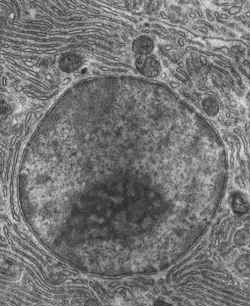

EL NÚCLEO CELULAR:

-Está formado por: Envoltura ó Membrana nuclear , por el nucleoplasma ó carioplasma que contiene macromoléculas y partículas que participan en la conservación de la célula, por la cromatina Contiene el material genético: ARN m- ARN t- ARN r).y por el nucléolo.

LA CROMATINA:

Es la carga genética localizada en el ADN, formada por proteínas básicas llamadas Histonas y pocas proteínas ácidas. Su condensación forman los Cromosomas, observable durante la mitosis.

HETEROCROMATINA: Molécula de ADN condensada es inactiva, por lo tanto no está en transcripción.

Se observa al Microscopio Óptico.

LA EUCROMATINA:

Molécula de ADN distendida, está en proceso de transcripción.

No se observa al Microscopio Óptico.